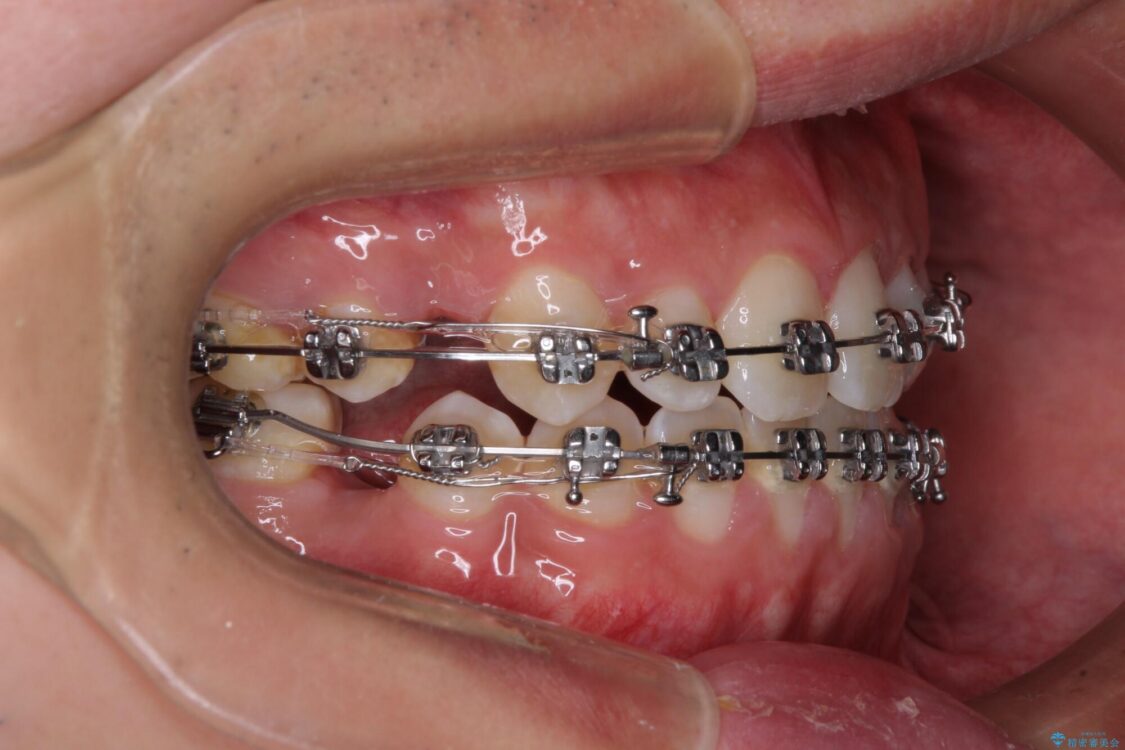

治療途中

• 口元の突出感を改善 受け口傾向の咬み合わせの抜歯矯正 治療途中画像

受け口傾向特有の狭い上顎歯列であったため、歯列の拡大を補助装置で行い、下顎歯列全体を後方に移動させることとしました。

奥歯の咬み合わせを改善させた後、上下左右の小臼歯(下顎は残存乳歯)を計4本抜歯し、ワイヤー装置にて口元の突出感を改善しながら咬み合わせを整えることとしました。

受け口傾向の方の抜歯矯正は、下顎前歯が舌側に倒れることで歯肉退縮を起こしやすいことが知られていますが、ワイヤーに工夫をすることでリスクを軽減させています。